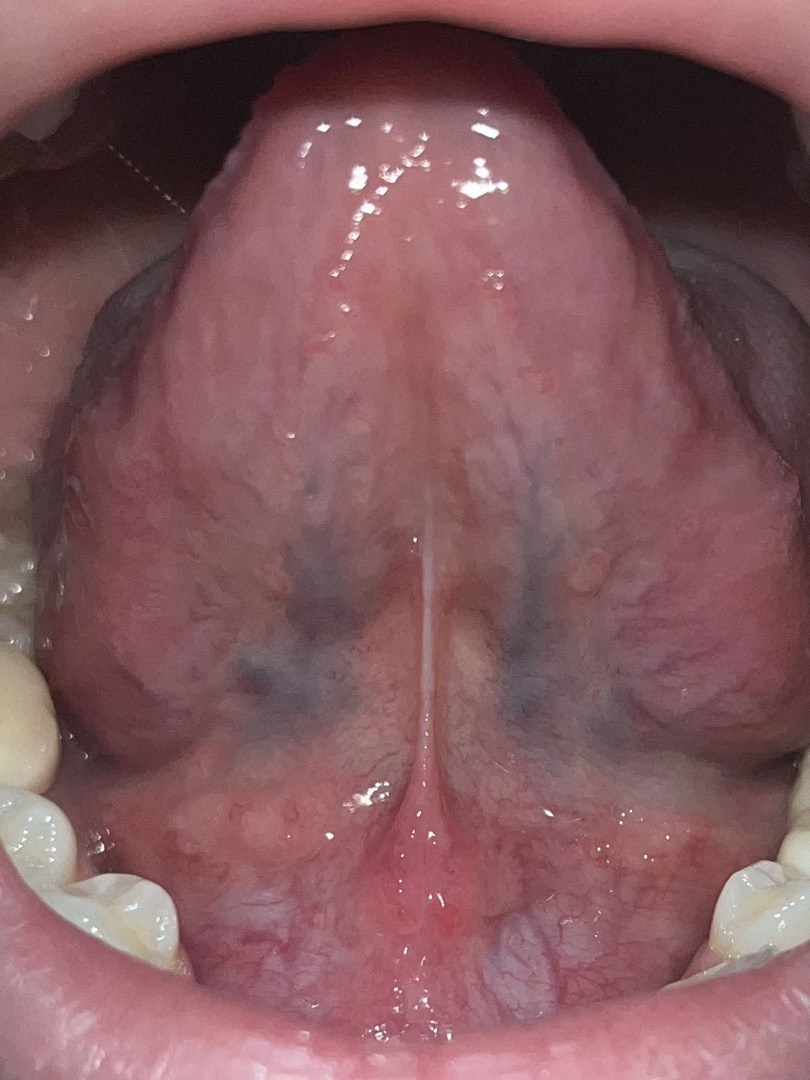

Mn ơi lưỡi em tự nhiên có mấy nốt đỏ vậy vs dưới lưỡi có nốt dài mọc đối xứng nhau. Đây có phải sùi mào gà k ạ, hay viêm gai lưỡi, hay là u nhú tiền đình ạ. Em có quan hệ bằng miệng vào tháng 1 năm ngoái và tháng 1 năm nay nên hơi lo. Nhưng dưới âm đạo không thấy biệu hiện gì cả. Hay do em ăn cay nóng ạ huhu. Lợi chỗ chân răng cũng có sưng loét ạ

Bạn ơi, mình hiểu cảm giác lo lắng của bạn khi thấy những nốt lạ trong miệng, đặc biệt khi có tiền sử quan hệ bằng miệng. Tuy nhiên, để biết chính xác có phải là sùi mào gà, viêm gai lưỡi, u nhú tiền đình hay chỉ là phản ứng do nóng trong, thiếu vitamin, hay viêm miệng lưỡi tạm thời, thì cần thăm khám trực tiếp hoặc soi tươi/ làm xét nghiệm HPV tại cơ sở y tế.